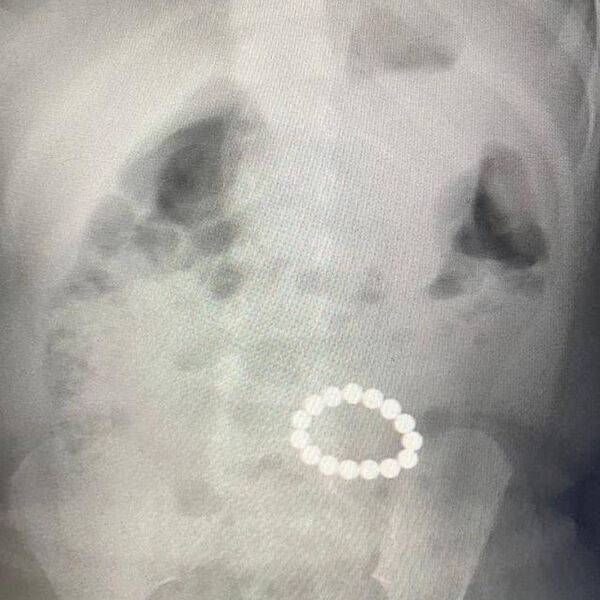

Девятимесячную пациентку доставили в медучреждение на скорой. Мать ребенка рассказала, что дочь съела несколько деталей от конструктора. Диагностика показала, что девочка проглотила гораздо больше деталей, чем предполагала ее родительница: рентген показал скопление в кишечнике 15 инородных предметов.